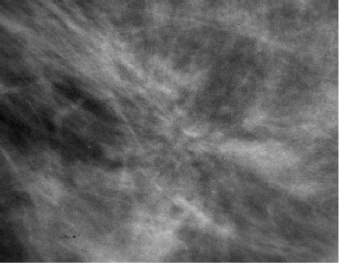

What does this histology section show?

Phyllodes Tumour (Leaf-like appearance)